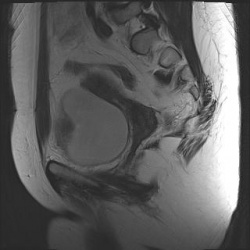

Полное удвоение матки. Случайная находка. Женщина рожавшая, была весьма удивлена.

24.06.2010 - 18:08

Достаточно редкое наблюдение - интрамуральная липома матки. T2 T1 Fat Sat

24.06.2010 - 17:51

Женщина, 40 лет. Жалобы на острые боли в малом тазу.Ваше мнение? Постконтрастный: